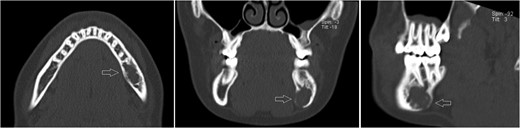

Axial, sagittal and coronar CT showing a 2 × 1 x 1.8-cm lesion in the left posterior mandible, its expansive and destructive character, and its penetration of the medial corticalis.